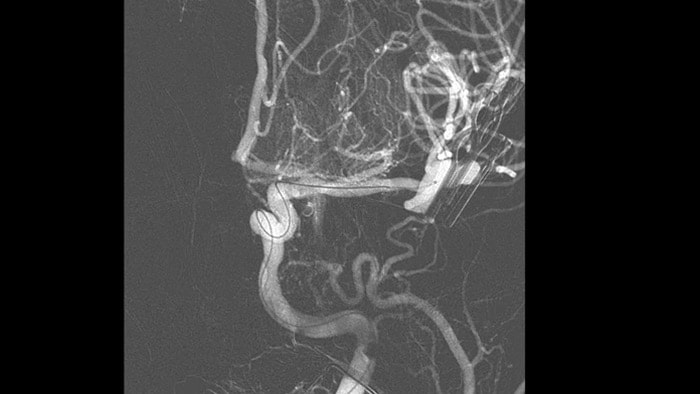

Poder evaluar de inmediato el impacto de los diversores de flujo es crucial durante el tratamiento. AneurysmFlow convierte la información de una adquisición de SmartCT Angio y las secuencias de flujo de la DSA 2D en valores de flujo cuantitativos.  Estos valores se utilizan para visualizar y cuantificar los patrones de flujo sanguíneo antes y después de la implantación del diversor de flujo en los aneurismas cerebrales.

SmartCT Angio proporciona una vista volumétrica en pocos segundos para ayudar a evaluar la ubicación, el tamaño, el cuello y la gravedad del aneurisma para la planificación del tratamiento. Los volúmenes 3D se ven con alta resolución espacial y compensación automática del movimiento del paciente.

AneurysmFlow evalúa los cambios en el flujo sanguíneo en el aneurisma; para ello calcula el cambio en la amplitud media del flujo del aneurisma (relación MAFA [Mean Aneurysm Flow Amplitude]) antes y después de la colocación del diversor de flujo.